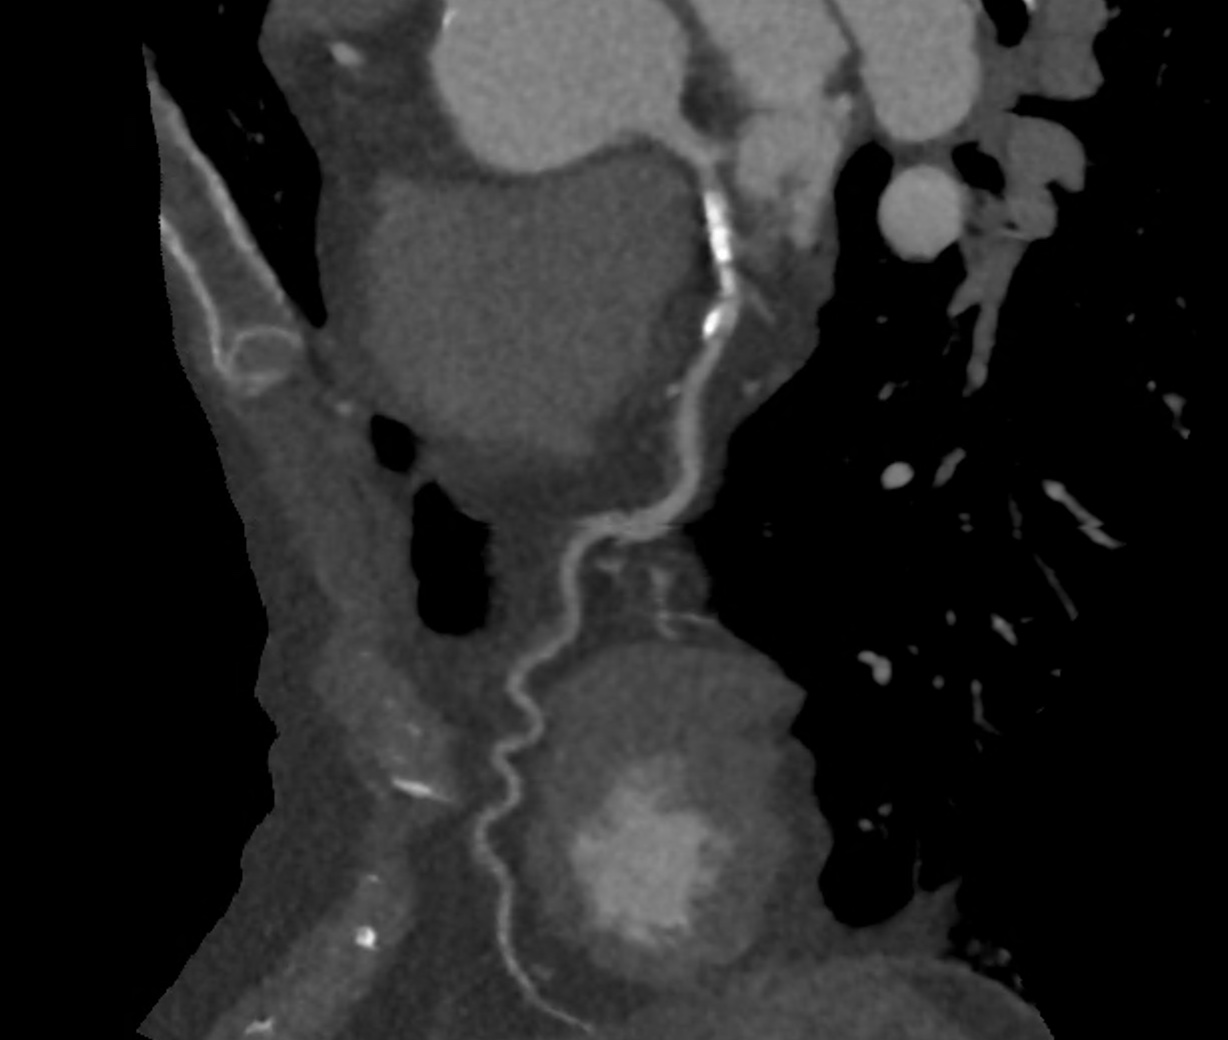

With the advent of multi-slice CT (MSCT), lower doses of radiation, and more medical interventions available to treat coronary disease, cardiologists are increasingly using CTCA to track the course of the disease particularly in higher-risk patients. It is now sometimes possible to observe changes in the same vessel of the same patient a few years apart. In the example shown below, the right coronary artery is affected close to its origin by non-calcified plaque, seen as an indentation in the vessel wall at the blue cross mark. The cross-sections are shown beneath, allowing comparison of diseased versus healthy sections (red cross mark). The indentation is caused by a crescentic atheromatous plaque, with low grayscale density, signifying soft or non-calcified plaque.

The figures below show the same patient’s right coronary artery after three years of taking statins. The plaque is still present; however, its volume is similar, and the density has changed to being ‘white,’ meaning that some of the plaque has calcified. This case illustrates the latest thinking, which is that the goal of modern prevention is to both prevent atheromatous plaque from developing and, once present, to accelerate the hardening and calcification of any soft or non-calcified plaque by prescribing statins. These drugs have multiple effects, the principal one being to lower LDL.

The same patient and artery after taking statin each day for 3 years.

In modern cardiology practice, the shift towards using advanced imaging techniques like MSCT has allowed us to provide more comprehensive care. In this single case, the patient’s right coronary artery showed significant non-calcified plaque. After three years of statin therapy, follow-up imaging showed that the plaque had begun to calcify, indicating a stabilising response.